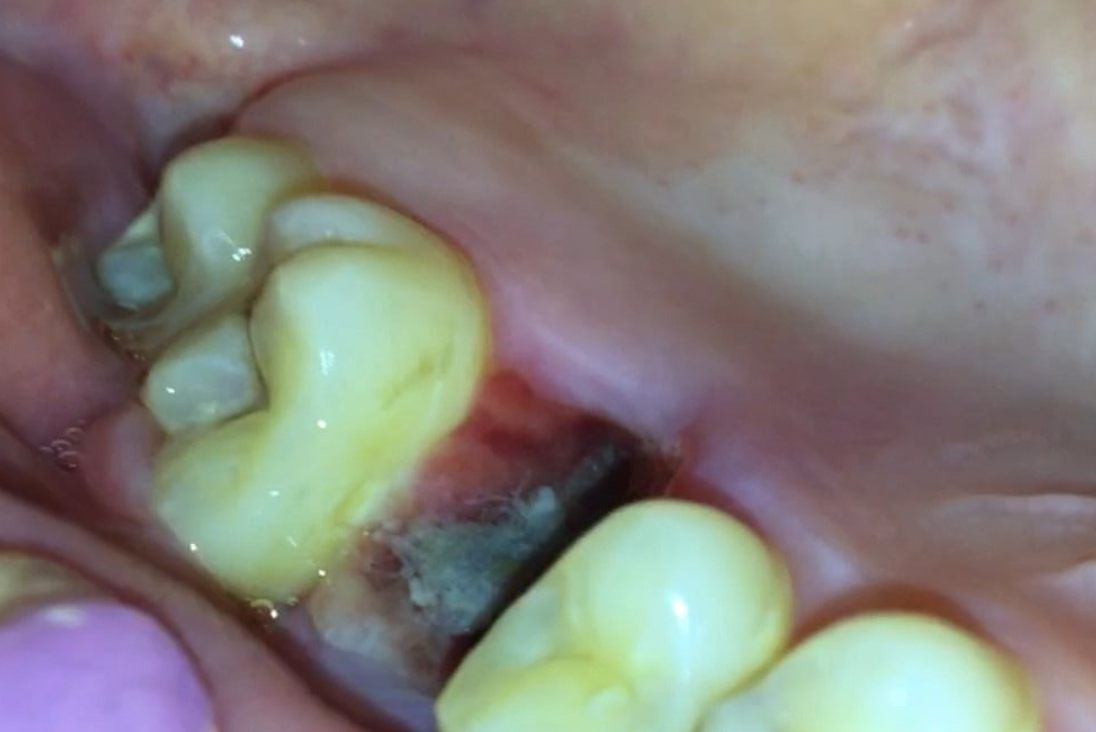

拔牙4天后出现血凝块掉落是一种正常的现象,多数情况下不会出现局部感染的现象。

拔牙4天后出现血凝块掉落,若同时伴随有明显出血等现象,则建议及时到医院就诊,看是否需要继续咬合医用无菌棉球止血,或观察是否出现感染等情况。

拔牙四天后一般会出现凝血块掉落,一般是不要紧的,绝大多数患者不会再次出现创面出血的现象,但极少数患者可能在进食后可能会出现局部疼痛、肿胀感,这可能是食物嵌塞引起,一般漱口或刷牙后就可缓解。